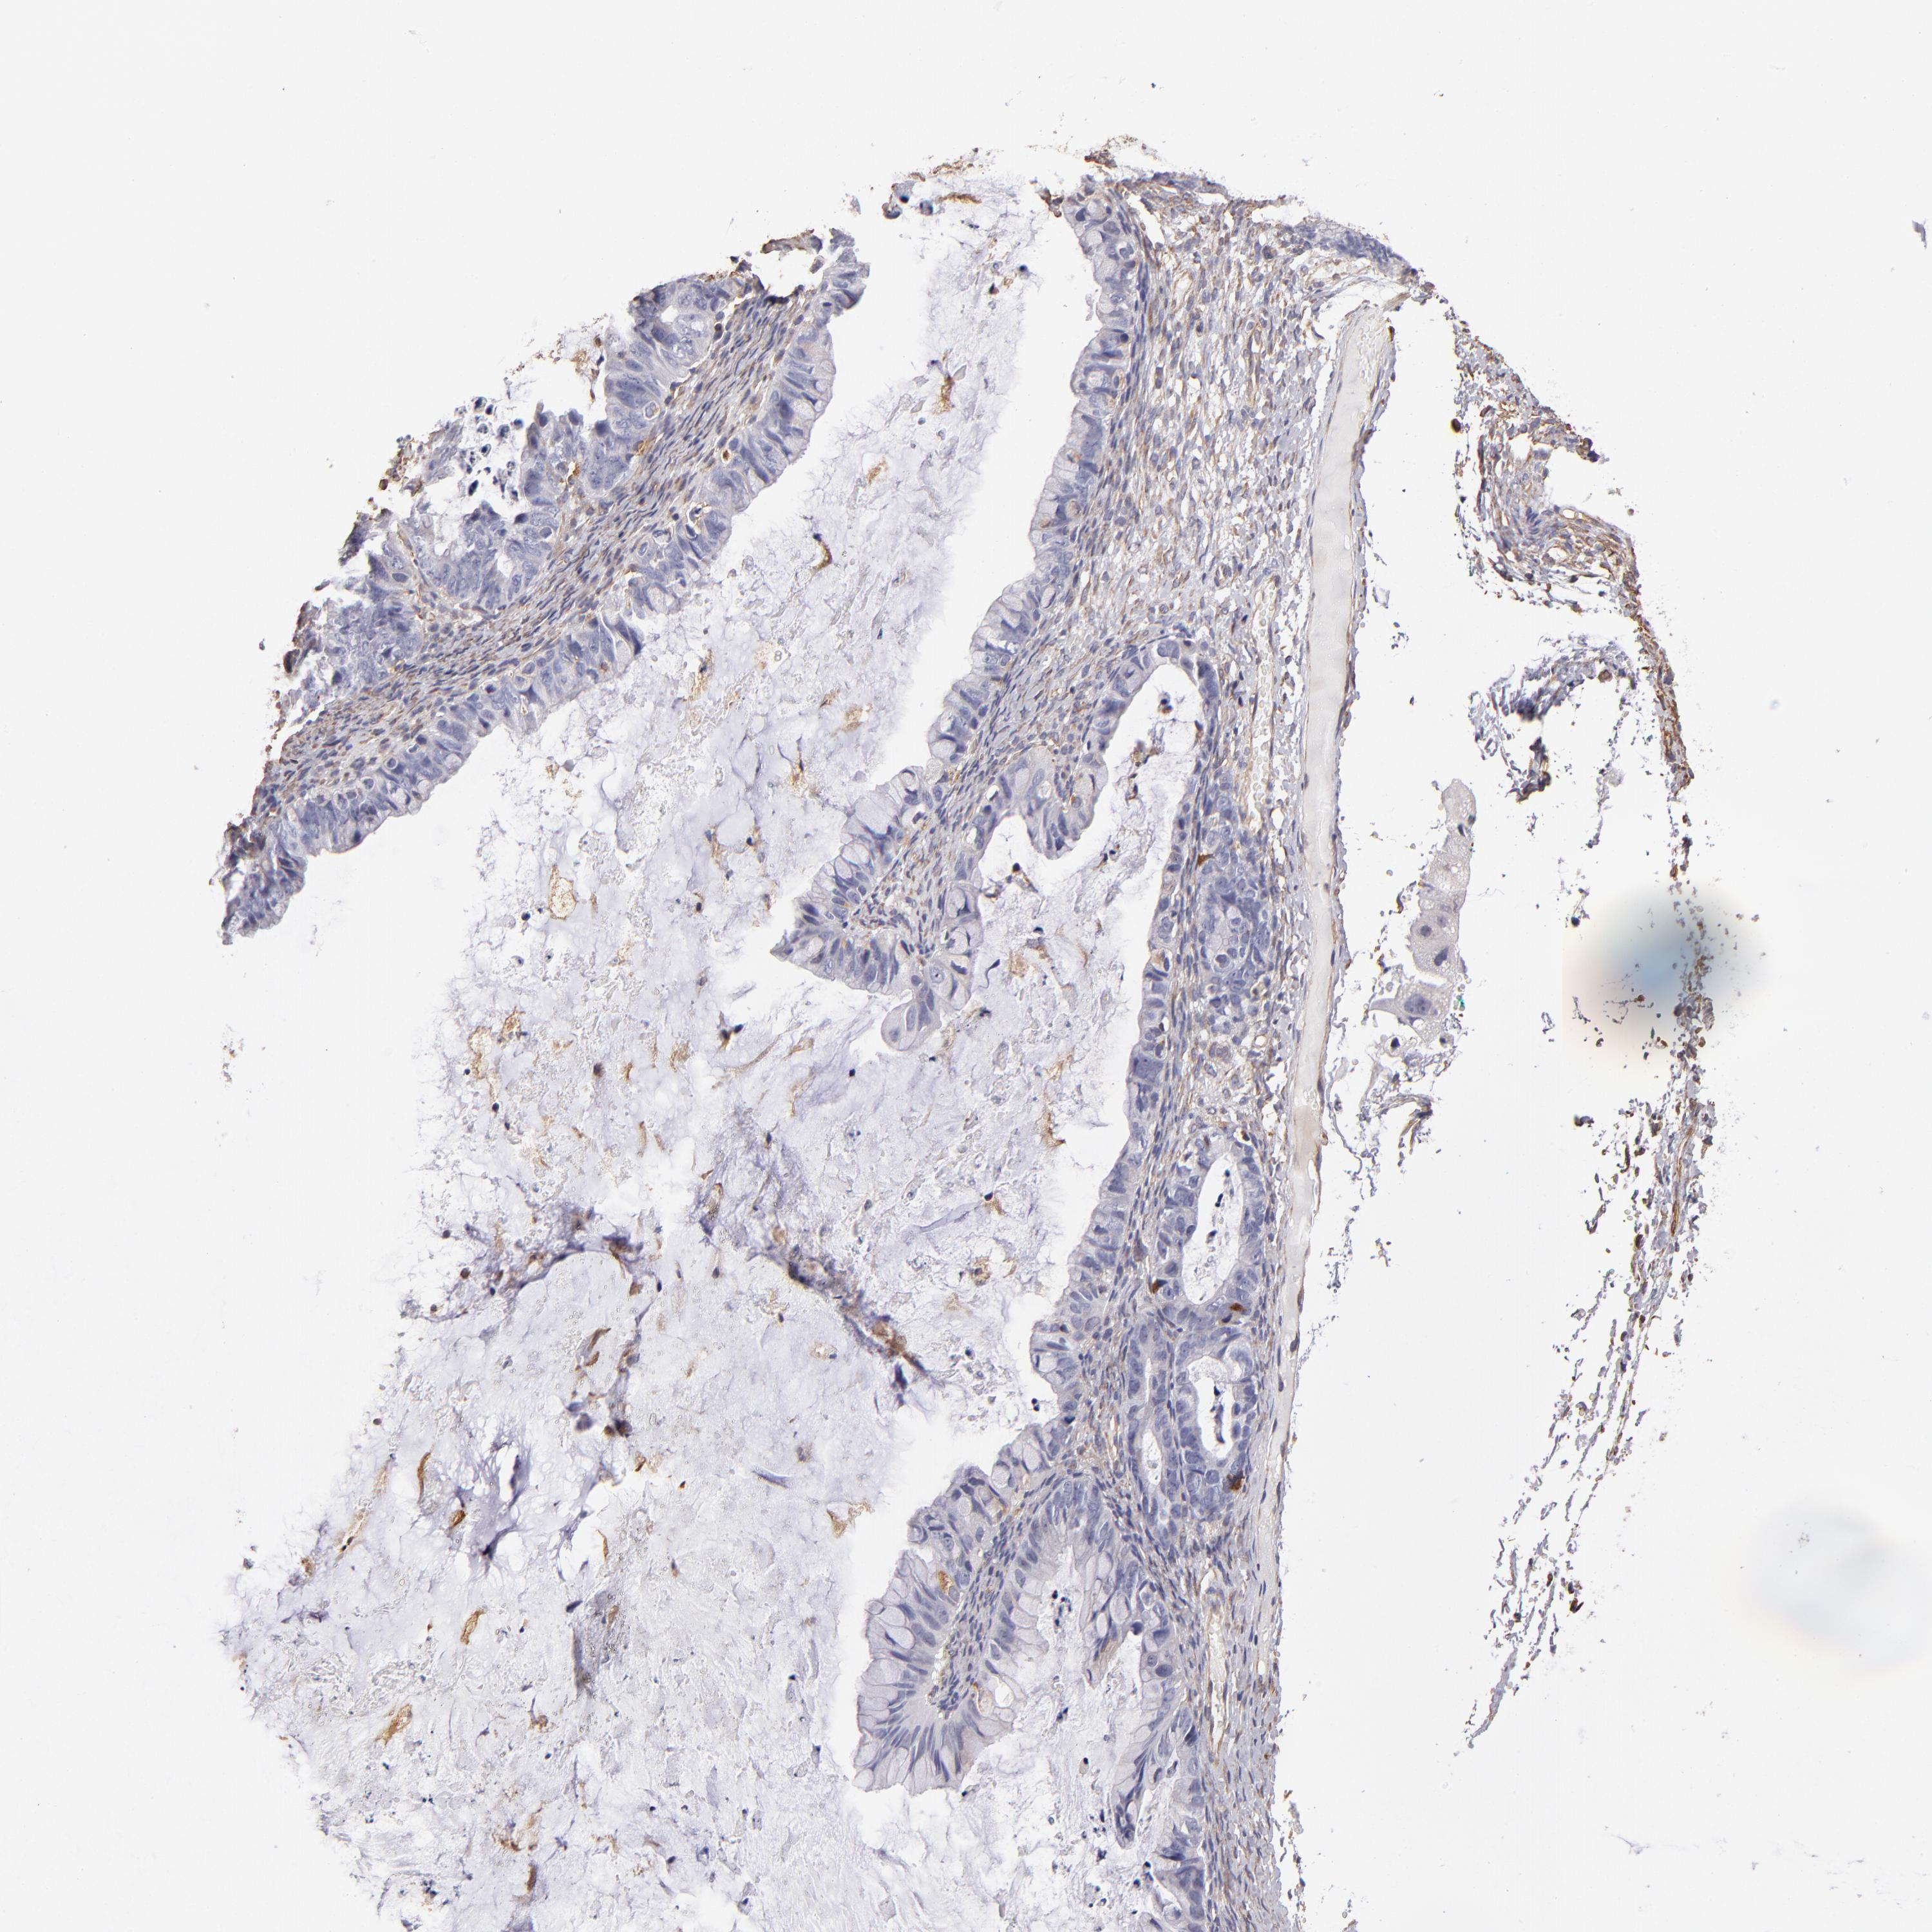

OVARIAN CANCER - Protein expressioni

A mouse-over function shows sample information and annotation data. Click on an image to view it in a full screen mode. Samples can be filtered based on level of antibody staining by selecting one or several of the following categories: high, medium, low and not detected. The assay and annotation is described here.

Note that samples used for immunohistochemistry by the Human Protein Atlas do not correspond to samples in the TCGA dataset.

Antibody stainingi

Antibody staining in the annotated cell types in the current human tissue is reported as not detected, low, medium, or high, based on conventional immunohistochemistry profiling in selected tissues. This score is based on the combination of the staining intensity and fraction of stained cells.

Each image is clickable and will lead to virtual microscopy that enables deeper exploration of all samples and also displays staining intensity scores, fraction scores and subcellular localization as well as patient and tissue information for each sample.

Antibody HPA002380

Staining

High

Medium

Low

Not detected

Intensity

Strong

Moderate

Weak

Negative

Quantity

>75%

75%-25%

<25%

None

Location

Nuclear

Cytoplasmic/membranous

Cytoplasmic/membranous,nuclear

Cystadenocarcinoma, serous, NOS

Cystadenocarcinoma, mucinous, NOS

Carcinoma, endometroid